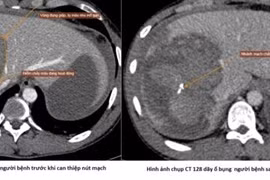

Nút mạch cứu sống người bệnh chấn thương gan nặng do tai nạn giao thông

Nút mạch cầm máu chấn thương gan – một kỹ thuật cao, ít xâm lấn, giúp kiểm soát chảy máu hiệu quả, hạn chế tối đa nguy cơ phẫu thuật mở.